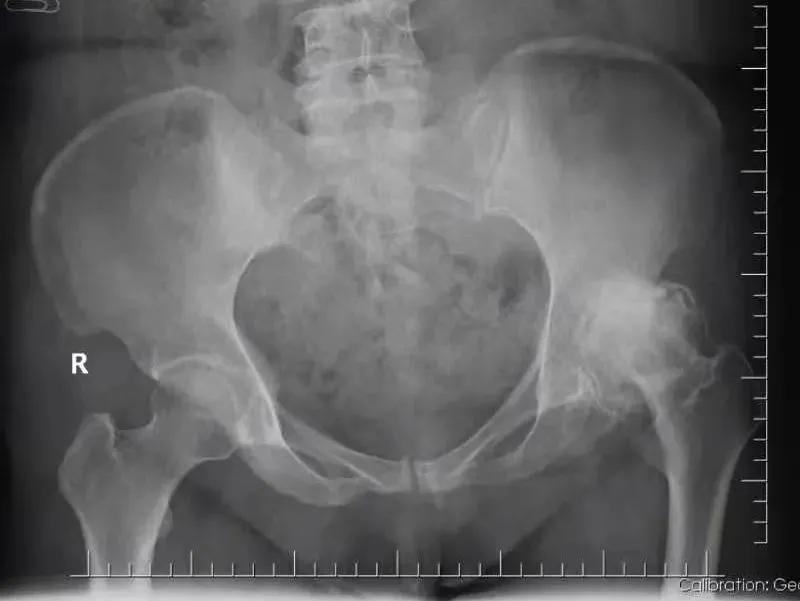

“间歇性疼痛,吃了很多止痛药,就没那么痛,没过多久又疼了,实在太难受了。”面对日益恶化的病情,张女士心急如焚。于是,张女士来到 佛山市第二人民医院骨一科 进一步诊治,通过骨盆X光片显示, 张女士左侧股骨头缺血性坏死 。

I期 X线平片无异常或见小的异常;

II期 X线平片显示股骨头内的囊变或硬化区域,股骨头轮廓正常;

III期 股骨头外形改变,髋关节间隙正常;

IV期 股骨头塌陷,扁平,关节间隙减小,髋臼退行性变,骨性关节炎。